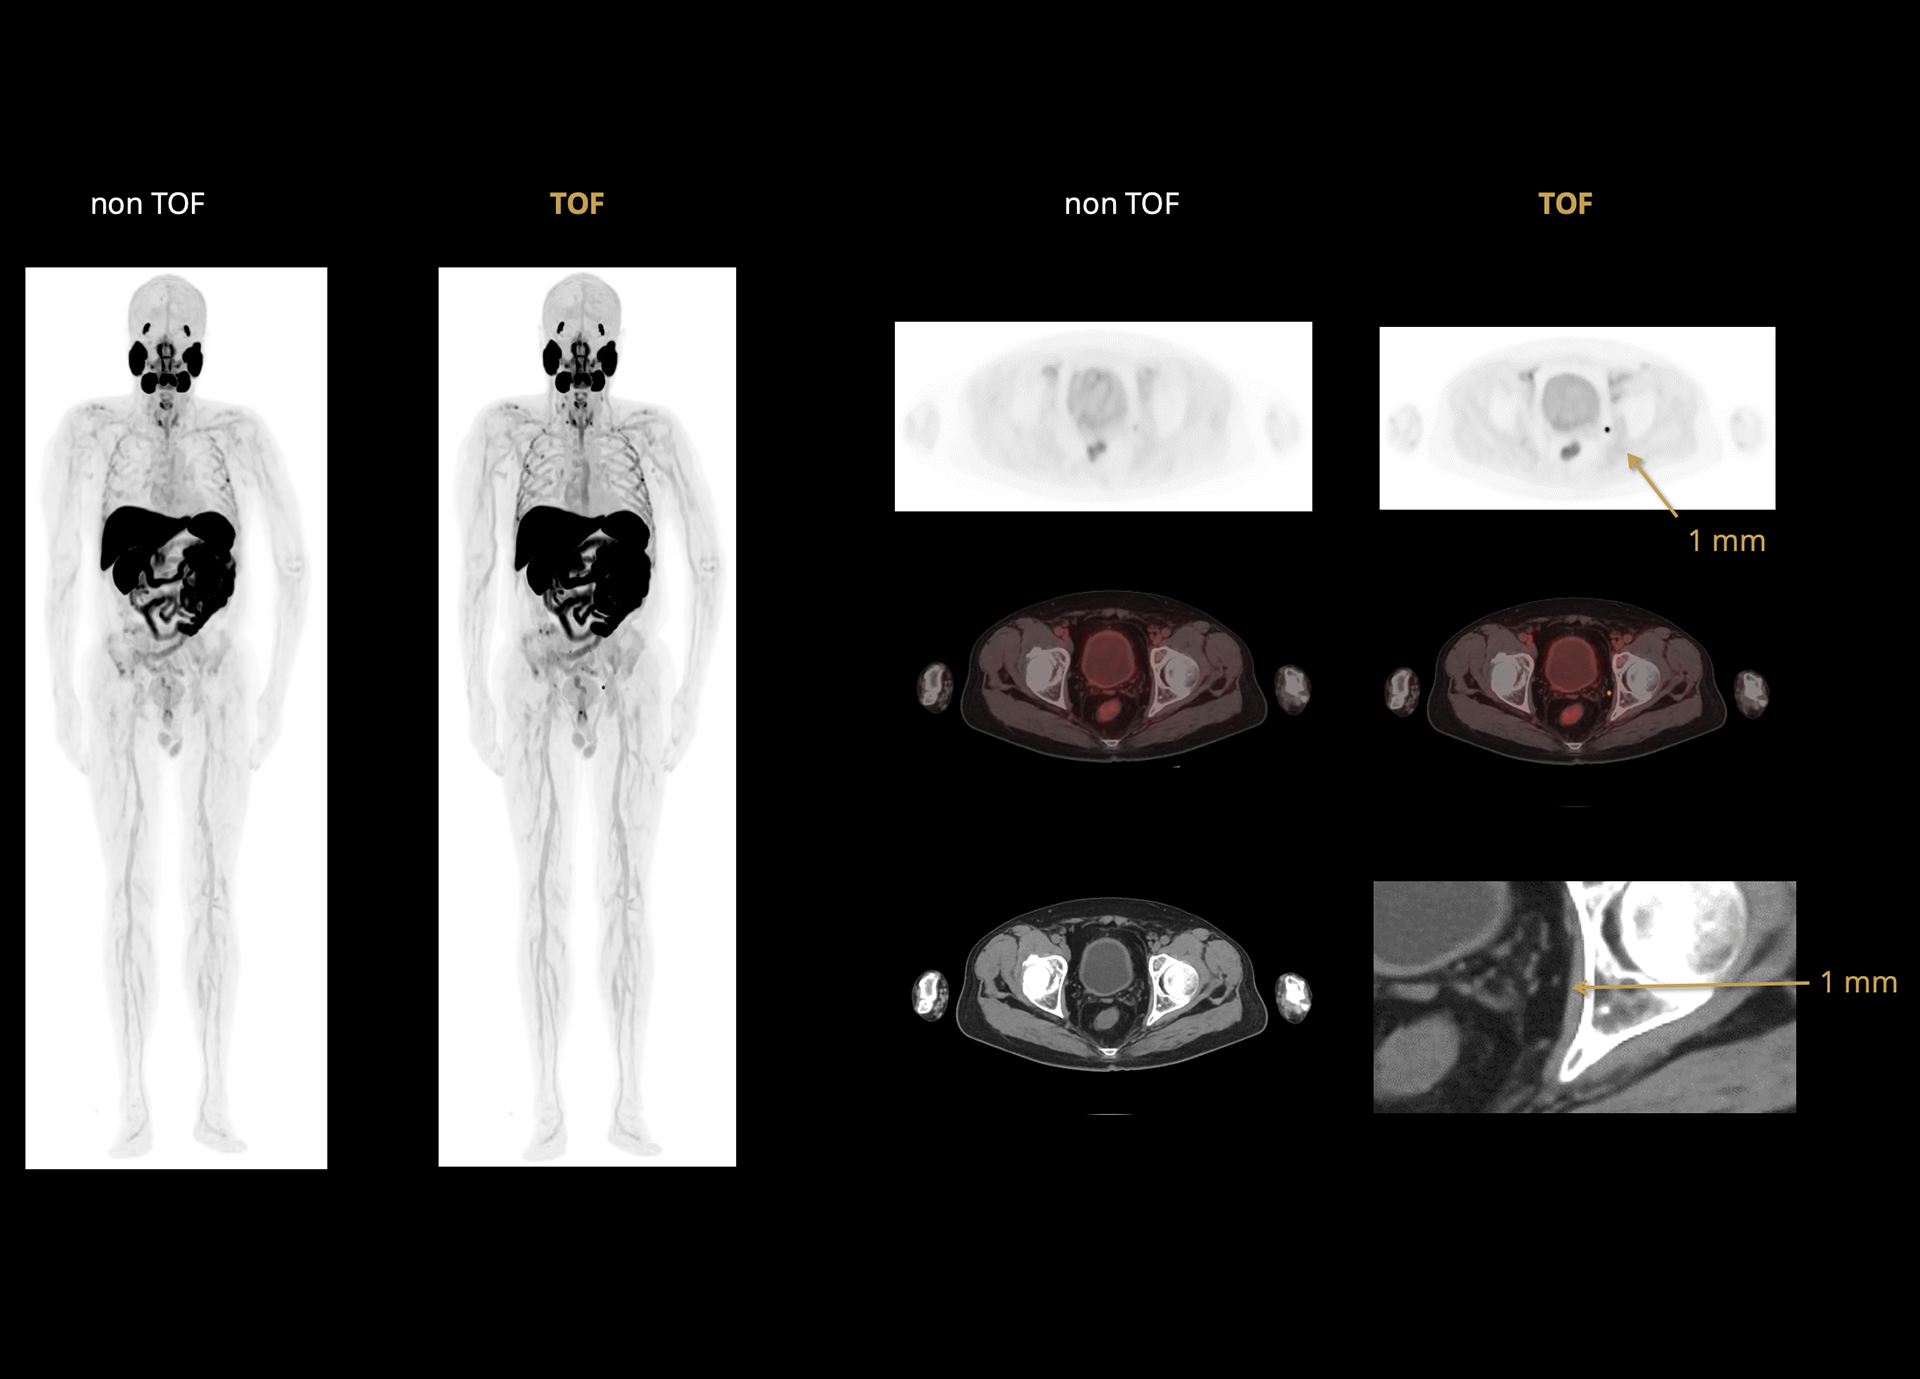

Leading TOF resolution that boosts small lesion detectability and clarity.